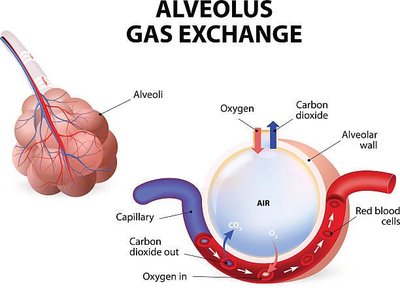

Alveoli are tiny air sacs where gas exchange occurs. They are surrounded by capillaries and have thin walls to facilitate diffusion.

Type I Alveolar Cells: Simple squamous cells forming the respiratory membrane.

Type II Alveolar Cells: Cuboidal cells that secrete surfactant to reduce surface tension.

Alveolar Macrophages: Remove debris and pathogens.

Alveolar Pores: Equalize air pressure and provide alternate air routes.

Gas exchange occurs by diffusion across the respiratory membrane. Oxygen moves from alveoli into blood, while carbon dioxide moves from blood into alveoli to be exhaled.

Respiratory Membrane: Formed by alveolar and capillary walls and their fused basal laminae.

Surfactant: Reduces surface tension, preventing alveolar collapse.